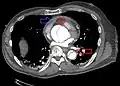

Computed tomography angiography is a fast, non-invasive test that gives an accurate three-dimensional view of the aorta. These images are produced by taking rapid, thin-cut slices of the chest and abdomen, and combining them in the computer to create cross-sectional slices. To delineate the aorta to the accuracy necessary to make the proper diagnosis, an iodinated contrast material is injected into a peripheral vein. Contrast is injected and the scan performed using a bolus tracking method. This type of scan is timed to injection to capture the contrast as it enters the aorta. The scan then follows the contrast as it flows through the vessel. It has a sensitivity of 96 to 100% and a specificity of 96 to 100%. Disadvantages include the need for iodinated contrast material and the inability to diagnose the site of the intimal tear.

CT with contrast demonstrating aneurysmal dilation and a dissection of the ascending aorta (type A Stanford)

Chest CT with descending (type B Stanford) aortic dissection (red circle)

Type A dissection with pericardial effusion as a result.